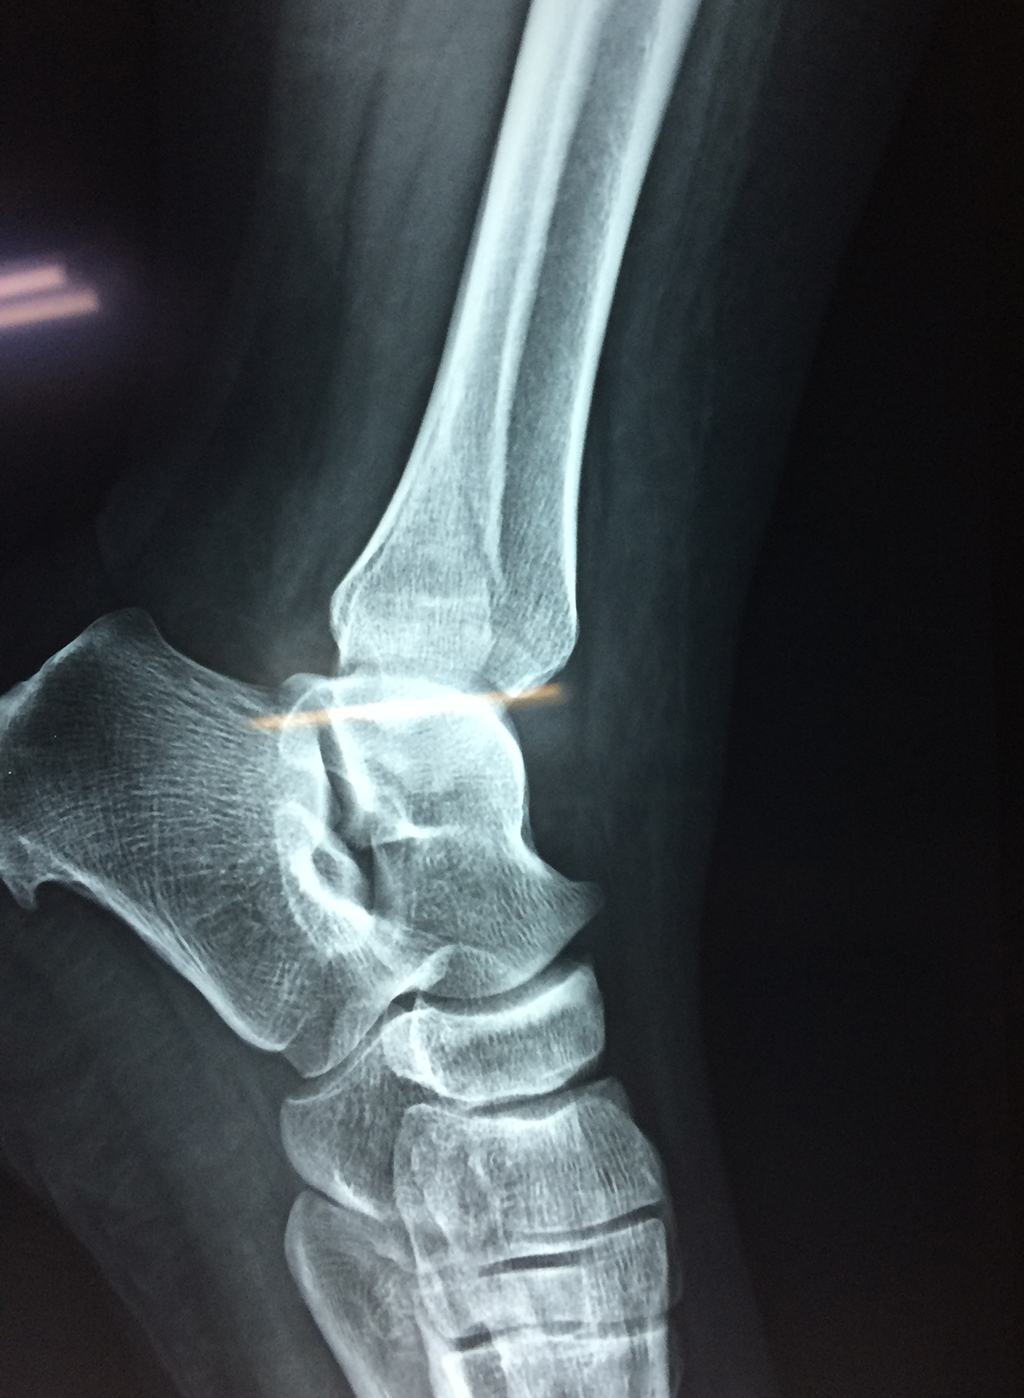

Una fractura de tobillo es la rotura de uno o más de los huesos del tobillo. Estas fracturas pueden ser:

- Los extremos de los huesos están desalineados entre sí (desplazados).

- La fractura se extiende hasta la articulación del tobillo (fractura intra-articular).

- Los tendones o ligamentos (tejidos que sujetan los músculos y los huesos entre sí) están rotos.